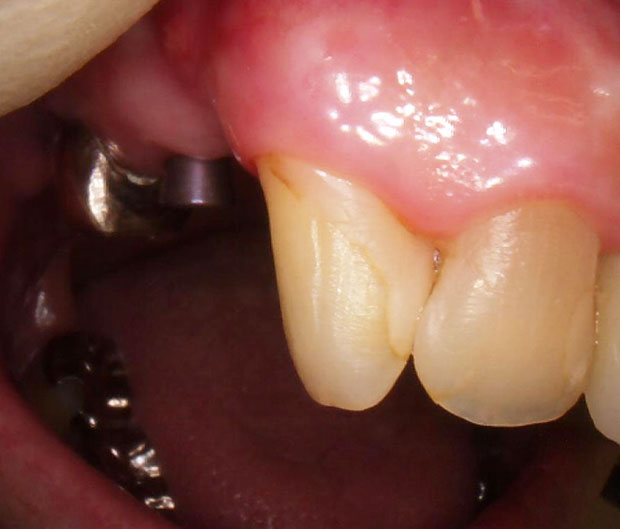

上物が入った状態です。

非常に綺麗にセットすることができました。

(4番目も銀歯で気になるとのことなので被せ直しました)